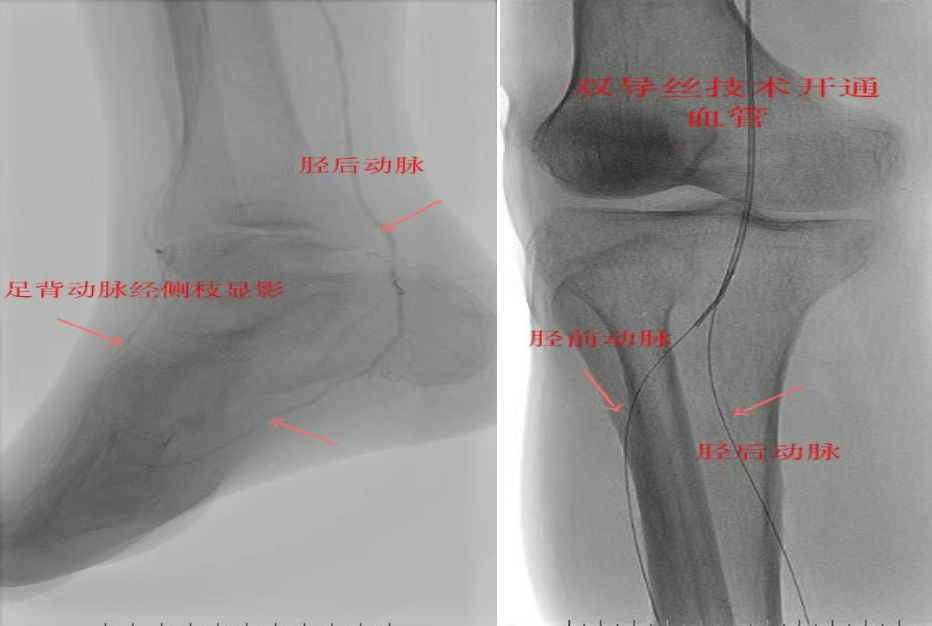

78岁男性患者,糖尿病合并高血压、脑梗塞,右足持续疼痛伴冰凉发绀3个月。入院CTA显示其右侧股浅动脉全程闭塞,膝下三支动脉均闭塞。医疗团队在局部麻醉下,再次巧妙应用“逆向开通技术”,经胫后动脉——足底弓逆向开通足背动脉及胫前动脉。术后患者右足皮温即刻回升,疼痛消失。术后结合中药外治(换药、熏洗、去腐生肌膏外敷)加速创面愈合,患者已顺利出院。

影像检查:CTA显示右侧股浅动脉全程闭塞,膝下三支动脉(胫前、胫后、腓动脉)完全闭塞。

两例患者共同凸显三大高难度治疗挑战:1.患者高龄且基础病复杂;2.血管全程多节段闭塞、钙化程度严重;3.常规顺向开通路径已被完全阻断。团队果断采用远端逆行穿刺技术,在纤细的足踝部血管建立治疗通道,实现“逆向破冰”。